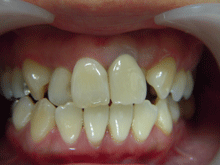

セ ラ ミ ッ ク ク ラ ウ ン

内面には金属を使用し、外面にセラミックを築成するタイプで、従来多くがこの方法で治療されていました。

症 例